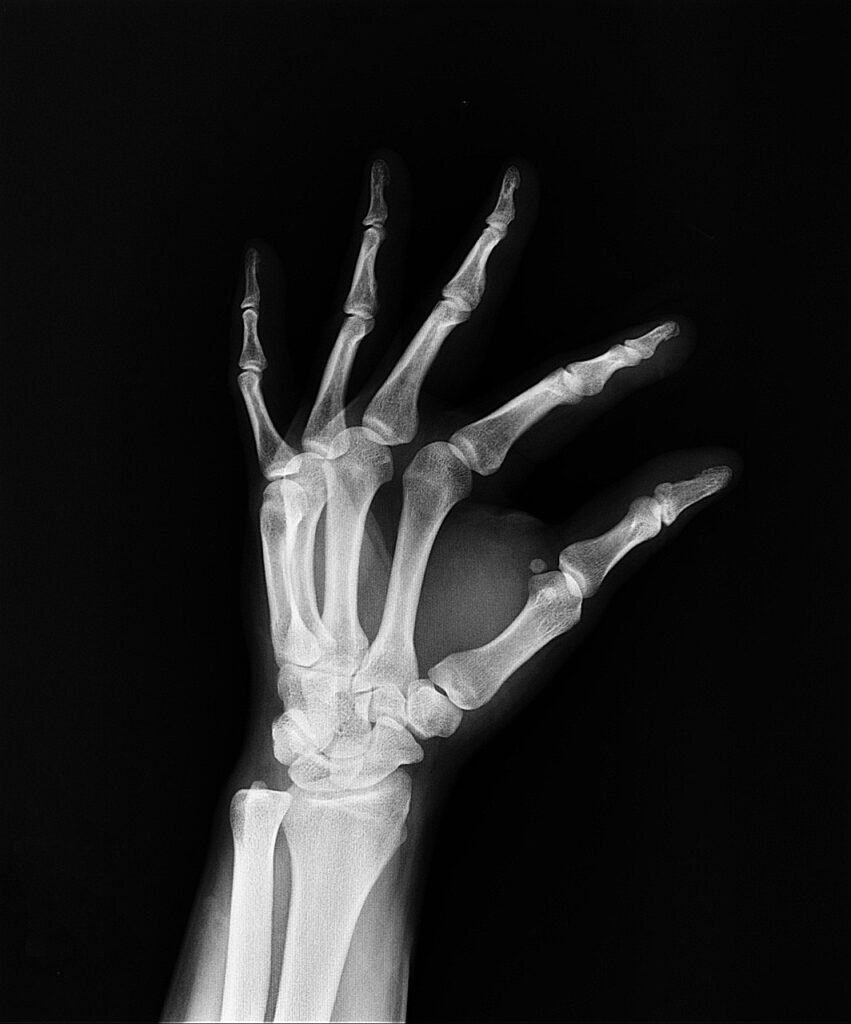

X-Ray:

The department offers digital X-ray imaging, which is used for assessing bone fractures, joint issues, lung infections, HSG, IVP, RGU+MCU, Barium test, Loopogram, Fistulogram, Sainogram and other conditions. Digital X-rays are quick and have better image quality than traditional X-rays.